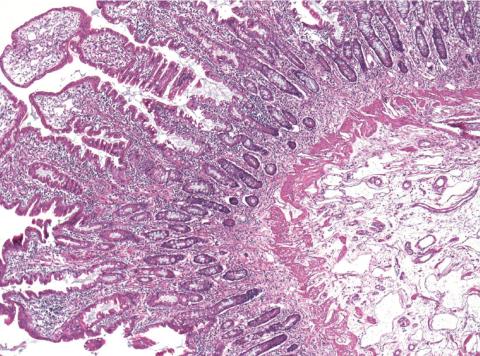

Shown is gut tissue of a child with CHAPLE disease. Large white areas at lower right are enlarged lymphatic vessels.

Recognizing the opportunity to further illuminate the rare condition, Lenardo and his colleagues analyzed the genes from 11 children with this subset of primary intestinal lymphangiectasia and their families. Each child had two copies of a defective gene called CD55 that prevented the production of a cell surface protein also called CD55. This protein helps regulate the immune system by blocking the activity of a group of proteins called complement.

Complement can help fight infections by punching holes in the cell membranes of bacteria and other infectious agents, but can also—if left unchecked—damage the body’s tissues. This unchecked complement activity, Lenardo explained, may account for the symptoms experienced by patients suffering an ailment they dubbed CHAPLE disease, or CD55 deficiency with hyperactivation of complement, angiopathic thrombosis and protein-losing enteropathy.